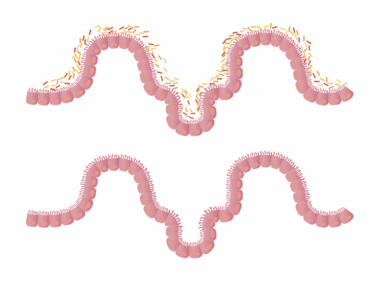

Research suggests that the body undergoes significant changes during fasting that can lead to enhanced digestive function. One notable process is autophagy. This process cleans cellular debris and dead cells, thus promoting healthier cell turnover. In turn, a more efficient digestive system is established as the body becomes better at handling digestive issues. Furthermore, fasting may stimulate the production of bile, which aids fat digestion. Thus, individuals who experience problems with fat digestion might find relief through fasting. Another potential benefit is improved gut permeability. When fasting occurs, the gut lining has the opportunity to heal, which is significant for individuals with leaky gut syndrome. Fasting encourages the growth of beneficial bacteria while suppressing harmful microorganisms, contributing to overall digestive health. Notably, before starting any fasting regimen, it’s essential for individuals to consult healthcare professionals. Specialized diets or fasting patterns that align with specific health requirements might be necessary for optimal results. These adaptations make fasting a tailored approach. With growing evidence supporting the benefits of fasting on digestive health, individuals can explore this potential solution with care and professional guidance.

Fasting may improve gut health through hormonal modulation. When fasting, levels of glucagon increase while insulin decreases, which fosters a more favorable environment for digestion. Lower insulin levels encourage the utilization of stored fat for energy instead of glucose. This metabolic switch supports more balanced energy levels throughout the day, leading to fewer cravings for unhealthy foods that may ignite digestive issues. Reduced insulin can also translate into decreased inflammation throughout the body, further aiding the digestive process. In addition, the increase in glucagon not only benefits overall metabolism but also supports liver function, ensuring proper bile production. Enhanced bile flow contributes significantly to fat digestion and absorption. Furthermore, fasting can promote appetite regulation through altering hormones such as leptin and ghrelin. By balancing these hormones, individuals may experience a decreased urge to overeat and an increase in mindfully selecting foods that nourish the digestive system. These physiological changes affirm the intricate relationships between hormones, metabolism, and digestion, suggesting fasting could serve as a powerful tool for those seeking improvements in their digestive health.